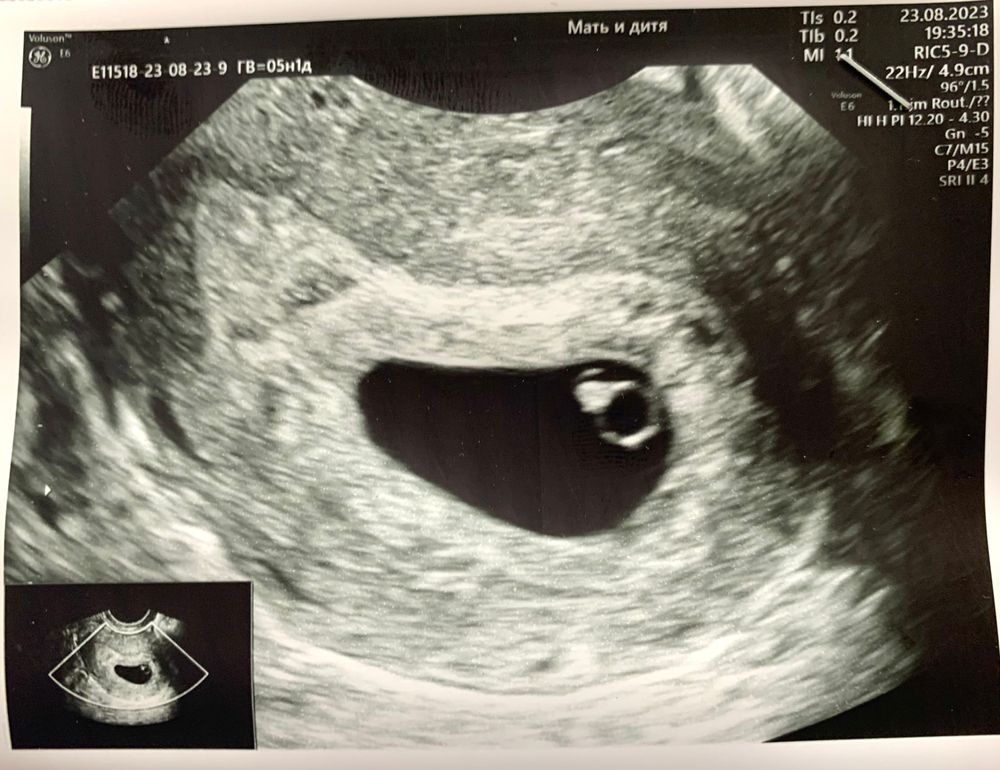

Весь день было все хорошо, и тут под конец рабочего дня пошли красные выделения, как месячные. Мужа в охапку и поехали, сначала в ПЦ, где нас отфутболили в городскую больницу, там еще хуже… УЗИ было сверху, ничего толком не увидели, отправили домой, сказали посмотреть дней через 10 🫠 Мы поехали в «Мать и дитя» на внеплановое УЗИ, и о чудо, все хорошо. Ни гематомы, ни отслойки, ни тонуса, и самое главное… Там уже есть эмбриончик 🥹

ПЯ 15.7мм

ЖМ 3.4мм

КТР 3.2мм

СБ 106 уд/мин